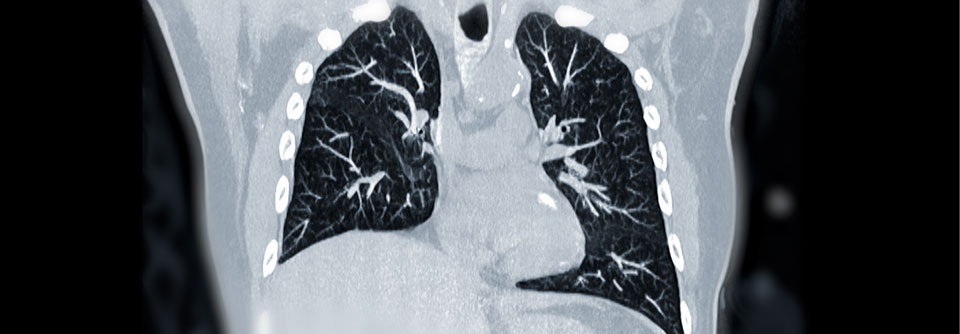

Bei 16 Personen (1,6 %) diagnostizierten die Forschenden – im Median nach 129 Tagen – mittels Rechtsherzkatheter eine CTEPH. Bei 16 Personen (1,6 %) diagnostizierten die Forschenden – im Median nach 129 Tagen – mittels Rechtsherzkatheter eine CTEPH. © tashatuvango – stock.adobe.com

Bei 16 Personen (1,6 %) diagnostizierten die Forschenden – im Median nach 129 Tagen – mittels Rechtsherzkatheter eine CTEPH. Die geschätzte kumulative Zwei-Jahres-Inzidenz betrug 2,3 %. Post-Lungenembolie-Einschränkungen gemäß der prädefinierten Kriterien traten mit einer kumulativen Zwei-Jahres-Inzidenz von 16 % auf. Sie lagen auch bei 15 der 16 CTEPH-Betroffenen vor. Wie die Studienautoren errechneten, steigt das CTEPH-Risiko bei Vorliegen dieser Kriterien um nahezu das Vierhundertfache an. Zudem haben Patienten mit Post-Lungenembolie-Einschränkungen ein erhöhtes Mortalitäts- und Rehospitalisierungsrisiko sowie eine geringere Lebensqualität.